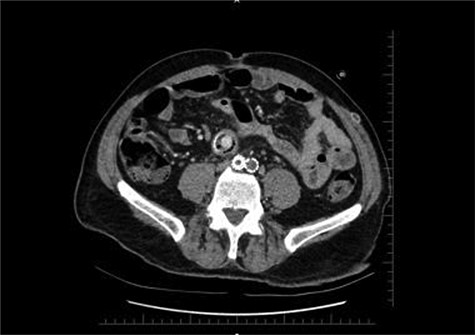

Axial section shows the two limbs of the EVAR, at the bottom. And on top of it, the Dacron straight graft part in the middle of the jejenum.

During the first days of December 2018, the patient visited another medical center because of fatigue, difficulty in breathing, lower back pain and inability to walk. His blood biochemistry revealed a very high CRP level (350 mg/dl), and complete blood count revealed a very high level of white blood cells (21 000/ul). An abdominal CT scan illustrated part of the graft was totally eroded into the small intestine (Figs 1–3). The patient was referred to my office and an infectious disease specialist. He had high body temperature (39.5°C) and was lying on the bed with lower extremities adducted to the chest. Antibiotic and supportive treatment was started. Emergency surgery was performed. We found an 8–10 cm of the straight part of the graft had become totally incorporated into the proximal part of the jejenum. The graft was freed, and 10–15 cm of the jejenum was resected and anastomosed. The area was irrigated with saline and hypochlorous acid. We then put a 20 x 10 composite mesh between the vascular graft and the intestine using a non-adhensive surface facing the intestine to prevent future graft and intestine interactions and erosion. After hemostasis, two drains were placed retroperitonally, and the abdomen was closed. On the fourth post-operative day, a high body temperature and high CRP levels were recorded. An abdominal CT revealed retroperitoneal abcess formation. During relaparotomy, the anastomosis was found to be intact, and the retroperitoneal abscess was drained and irrigated with saline. The drains were reinserted. After a month, he once again started to have high fever and high CRP levels. Again, an abdominal CT revealed abscess formation. This time, the abscess was approached transcutaneously. By making an incision in the proximal left lomber region, the abscess was drained. Another incision was made distally, and two drains were placed in the retroperitoneal area.